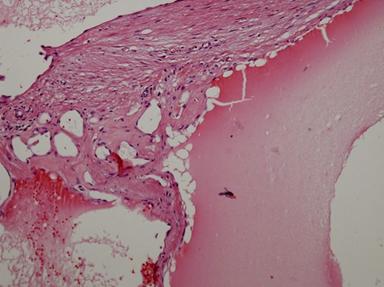

However, it did not show any demonstrable 18F-FDG uptake. Despite no evidence of malignancy or adrenal dysfunction, the tumor was scheduled to be removed surgically because of the symptoms caused by mass effect. She underwent laparoscopic adrenalectomy. At surgery, a round tumor was seen, encapsulated in a dense fibrotic tissue, which was easily dissected from the surrounding organs without invasion (Figure 3). The cut surface showed most of the mass to be spongy and yellowish with central areas of recent hemorrhage. Microscopically, the mass was composed of sinusoidal dilatation and fibrotic septa. Strong positive immunostaining for CD31 and CD34 with weakly positive staining for podoplanin/D2-40 supported the diagnosis of cavernous hemangioma (Figure 4). There was no evidence of malignancy.

Figure 4. A representative tissue section from the main region of the cavernous hemangioma. The vessel walls were cystically dilatated and thin. But, those may occasionally be thickened secondary to fibrosis. [hematoxylin and eosin (HE), magnification x 200]. |